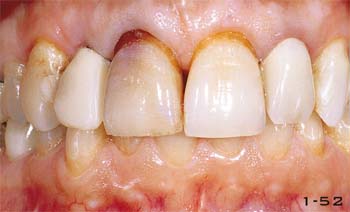

Abb. 1-52 Provisorische Kronen in situ (s. Kap. 7 u. 8). In dieser Phase können die devitalen Zähne gebleicht werden.